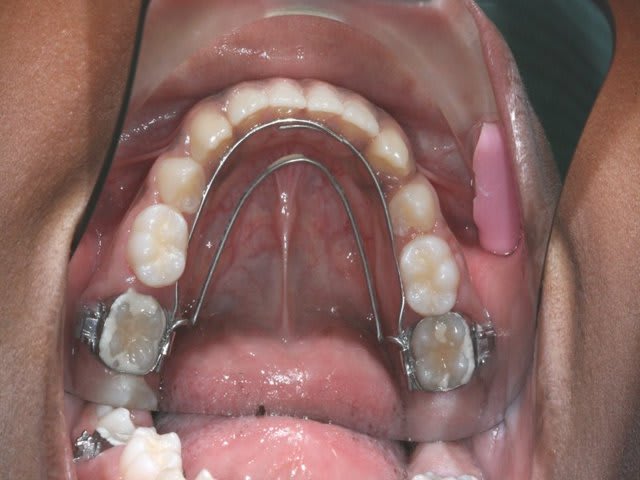

je tente donc un Q.H. Crozat, sans rien d’autre

à suivre

Img 1 dz8npb - Eugenol